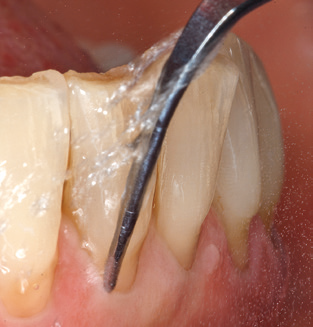

Good illumination of the working field facilitates the process considerably. The system used by the authors achieves this thanks to a 5x LED ring integrated in the handpiece. Naturally, a range of working tips for different indications is also offered. A straight, universally employable tip is the basic instrument required for machine cleaning of natural teeth (Fig. 5a and b). Curved tips, which allow access to exposed furcations, are also available for hard-to-reach areas in the posterior region (Fig. 6).